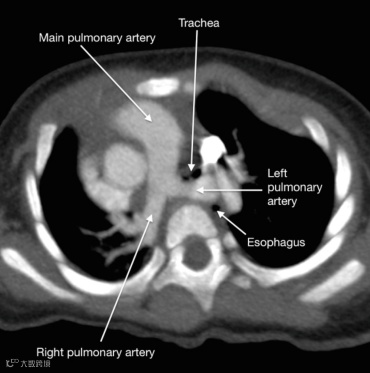

肺动脉吊带(pulmonary arter sling, PAS)又称先天性迷走左肺动脉,是一种罕见的先天性心血管畸形。其病理表现为左肺动脉起源于右肺动脉,走行在食管与气管之间,并环绕气管远段或右侧主支气管,到达左侧肺门,在气管远端和主支气管近端形成吊带,因此又被称为“吊带畸形”。

肺动脉吊带(箭头)